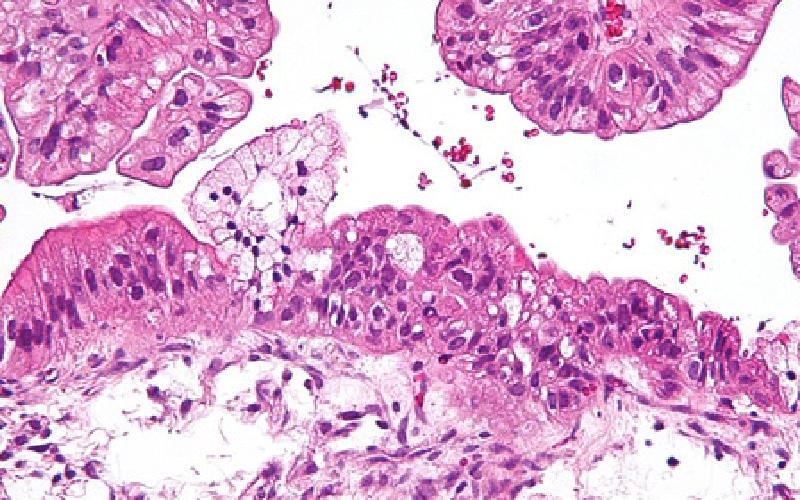

La Vannetaise soutient la recherche…